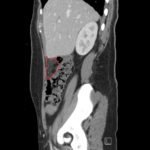

Fitz-Hugh Curtis syndrome (FHCS) is a rare sequela of pelvic inflammatory disease that must be included on the differential in patients with abdominal pain, particularly if they have risk factors for sexually transmitted infections. In this case, a 25-year-old female with a past history of Chlamydia presented to the emergency department with vaginal discharge and right upper quadrant pain. Complete blood count showed a mild leukocytosis, and computed tomography demonstrated fat stranding inferior to the liver and along the right colon. The patient was diagnosed with Fitz-Hugh Curtis syndrome and admitted for intravenous (IV) antibiotics. After 48 hours of IV antibiotics she was discharged with a 14-day course of doxycycline and metronidazole. Multiple bacterial species have been implicated in FHCS, including but not limited to Chlamydia trachomatis, Neisseria gonorrheae, Mycoplasma genitalium, Peptostreptococcus spp., and Prevotella spp. Therefore, careful consideration should be given to the choice of antimicrobial treatment.